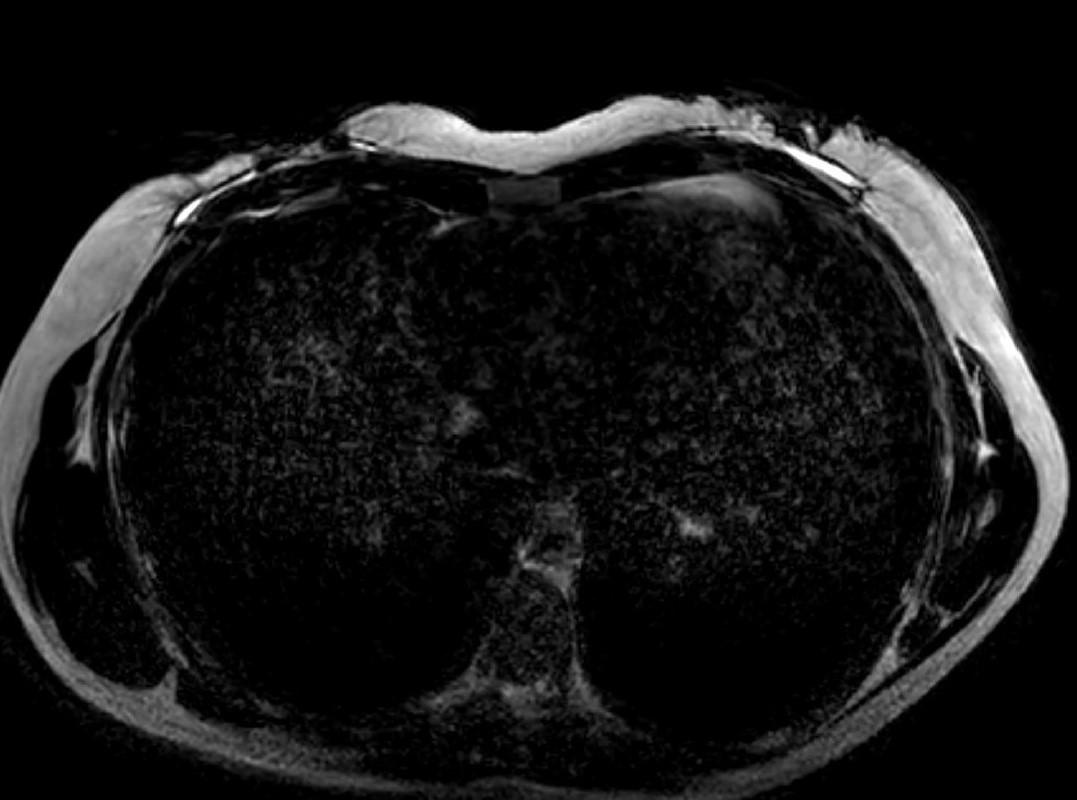

2023年的乳腺MRI检查可以看到双侧全乳重建术后自体脂肪移植(AFT)的效果,其表现为双侧乳晕后异质性肿块。

轴位T1WI图像(图4)及对比增强T1WI脂肪抑制图像(图5)显示,肿块中心见含脂肿块,边缘环绕着薄薄的强化带。